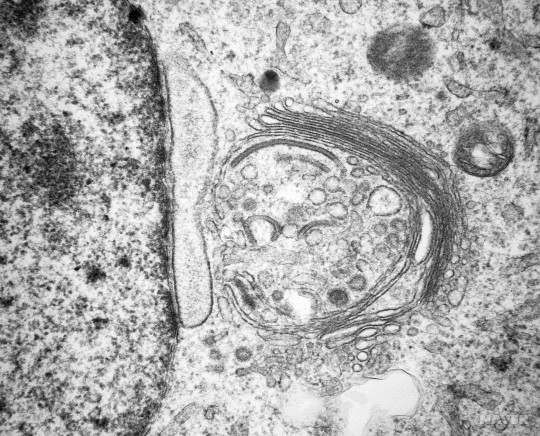

: 비교적 새롭게 제안된 전립선암의 marker 로, 골지체 막단백질의 일종이에요

참고로, 골지체는 세포 소기관으로, 이렇게 생겼답니다⬇️ (많이 본 적이 있을 거에요.. 꽤나 인상깊게 생겼거든요)